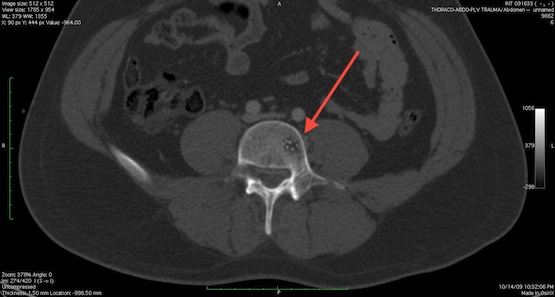

Аневризматическая костная киста |

Новообразование чаще всего встречается в шейном отделе, но может наблюдаться и в поясничном. Обычно появляются у подростков в пубертатный период, лечатся преимущественно оперативным путем. |

Метастазы в позвоночник

Саркома Юинга

Если речь идет о вторичных опухолях, то чаще всего метастазы в костные ткани дают злокачественные заболевания молочных желез, простаты, почек, щитовидной железы и респираторных органов. Пропальпировать новообразование на позвоночном столбе при раке можно только в том случае, если оно растет в переднем направлении – в иных случаях его можно обнаружить только при диагностике или на поздних стадиях, когда опухоль достигла достаточно больших размеров. Ранние этапы раковых болезней зачастую протекают бессимптомно, поэтому их обнаруживают достаточно поздно.